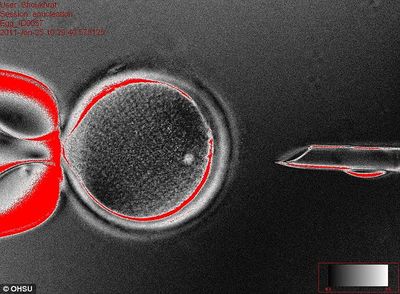

البيضة المانحة التى تسقط بواسطة ماصة قبل استخراج النووية في بداية عملية جذرية جديدة: اختراق يمكن أن يؤدي إلى تخصيص الخلايا للمساعدة في علاج حتى مجموعة من الأمراض

أولا، أخذ الدكتور ميتاليبوف Shoukhrat بويضات متبرع بها من قبل شابات بصحة جيدة وإزال الحمض النووي.

ثم وضع حينئذ خلايا الجلد داخل البويضات التى أزيل منها الحمض النووى واستخدم تيار ضئيل من الكهرباء لجعلها تبدأ النمو إلى جنين .

خلال نقل نواة الخلية الجسدية (SCNT)، يتم نقل نواة الخلية المانحة إلى خلية البويضة التي تم إزالة الحمض النووي النووية الخاصة.